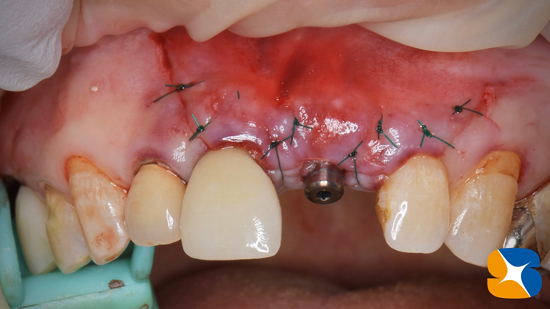

砕けた歯根を抜歯した後、続けてインプラントを同日に移植しました。

CGFと骨の誘発材(β−TCP)を使って、アゴ骨と歯肉の早期再生・回復を促しました。

使用インプラント:スプライン直径3.75㎜、高さ11.5㎜

手術から2ヶ月後の状態です。綺麗に歯肉が整い、アゴ骨も回復しています。

最初の手術から3ヶ月強でインプラントの歯が完成しました。